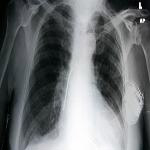

A pacemaker is a small device that doctors place in people with an abnormal heartbeat. If a heart beats too slowly, the pacemaker will use electrical signals to help set a normal rate. Some devices include a defibrillator, which gives a shock if the heart beats too fast.

Pacemakers may be permanent or temporary. But one thing is sure. Developing countries need more of them as more people get heart disease.

A big problem, however, is the cost. Buying and implanting a pacemaker costs from 5,000 to 15,000 dollars.

But doctors at the University of Michigan think they know a way to lower that cost. The idea is to reuse pacemakers.

Heart doctor Timir Baman estimates that more than one million people worldwide need pacemakers each year. He says reusing a pacemaker is an ethical way to provide health care to those who have no other way to get one.